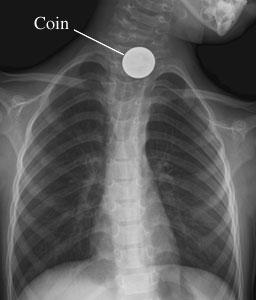

Chest X-Ray of a Swallowed Object

Front view of a child's chest X-ray shows a swallowed coin.